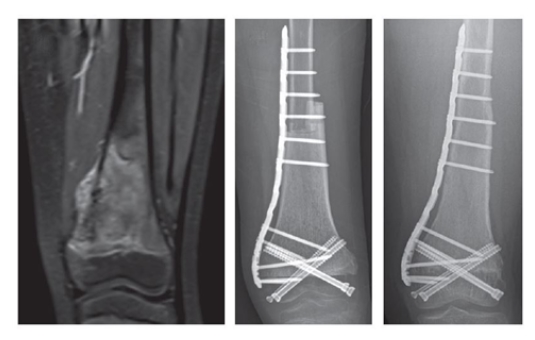

서울대병원 정형외과 김한수 교수팀(한일규·김용성)은 청소년 골육종 환자의 새로운 수술법 (골단판내 절제술, Transepiphyseal resection)을 개발했다. 관절은 보존하면서 종양이 있는 부분만 골라 제거하는 획기적인 방법이다. 연구팀은 해당 수술의 치료성과를 담은 논문을 23일 발표했다.

이때 연구팀은 수술 전 항암치료효과가 좋은 환자를 대상으로, 관절을 구성하는 뼈 부분은 보존하면서도 종양이 있는 뼈 부분만 제거했다. 종양이 있던 위치는 조직기증으로 확보한 타인의 뼈를 이식해 개건했다.

종양을 제거한 부위는 골이식을 통해 개건했다. 해당 환자의 무릎관절운동은 완벽하게 정상수준까지 회복됐다.